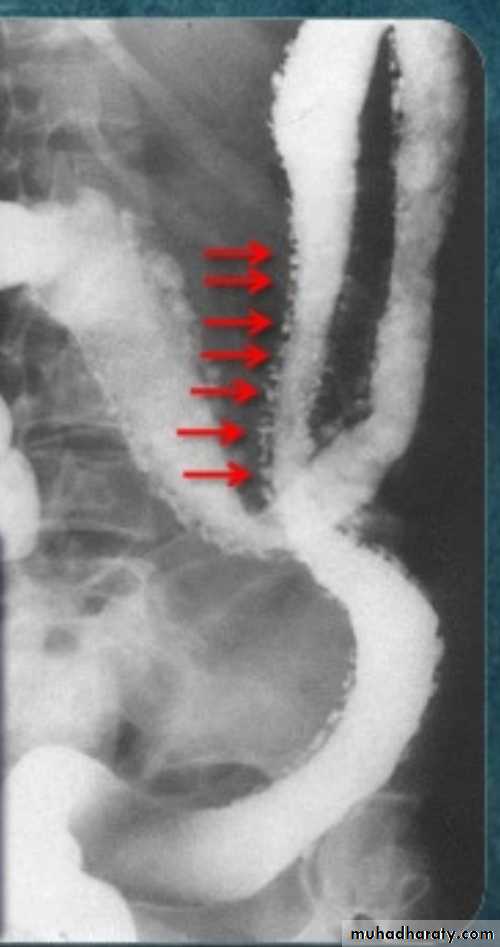

Ba enema

• Morphological types:• 1_ Ulcerative : give rise to irregularity of the colon with ulceration.

• 2_ Constrictive or infiltrative ( Annular ) type :

• a- Constant narrowing .

• b-Shouldering sign, apple core sign .

• c- Destruction of mucosa at narrow area .

• d- Double track due to fistula .

• e- In severe constriction ; stoppage of Ba. Flow with proximal dilatation .

3_Proliferative type : give rise to :

a- Large , constant filling defect with irregular margin .

b- Destruction of mucosa .

c- Intestinal obstruction

apple core lesion in the descending colon